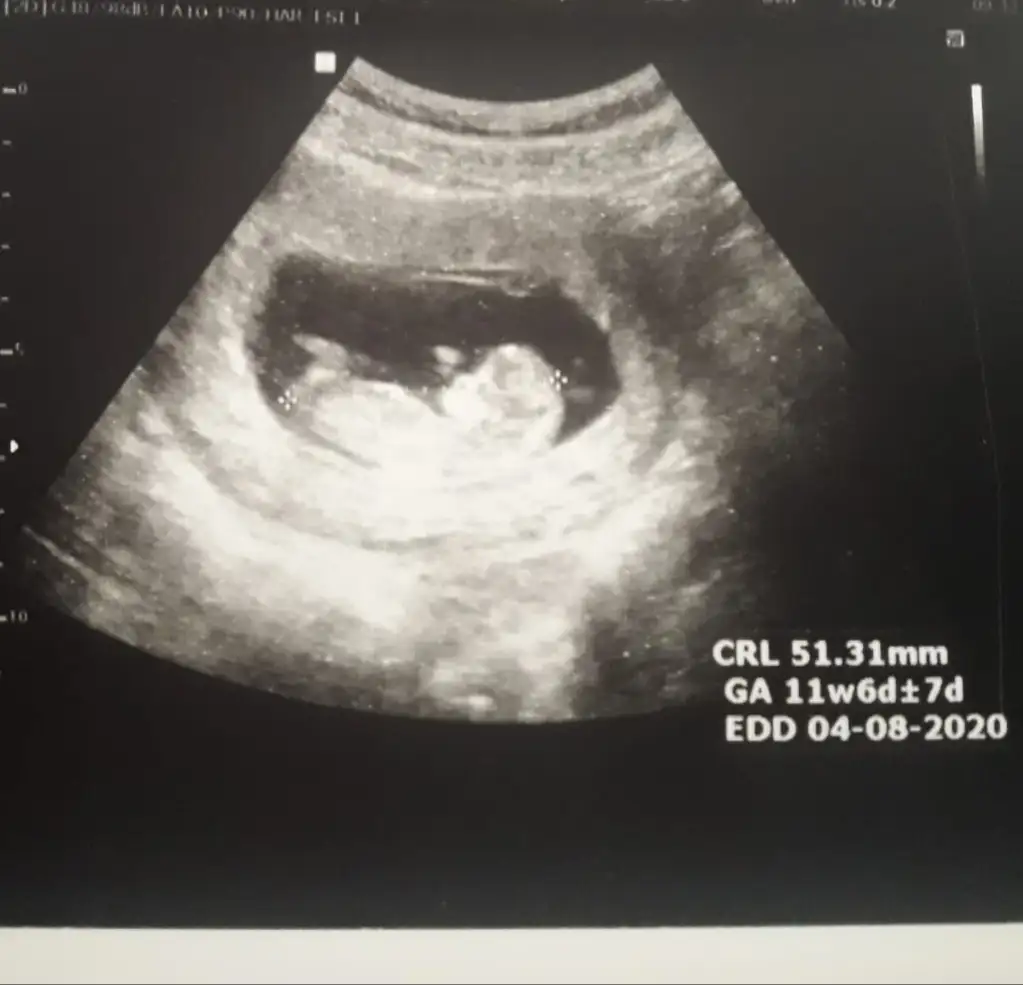

Dik canım parelek olsa kız derdim tabi benimki tahmin inşallah gönlünüzdeki olur işk bebekmiKızlar doktor çok erken dedi ama ben videoya çektim bugün burada nubu belli 11+0 bugün sizce nedir cinsiyet

Erkek gibi12 haftalık görüntü bize de bakarmısınız

Erkek diyorumKızlar doktor çok erken dedi ama ben videoya çektim bugün burada nubu belli 11+0 bugün sizce nedir cinsiyet

Kaç haftalıkMrb bu arkadaşımın ultrason görüntüsü bakar mısınız